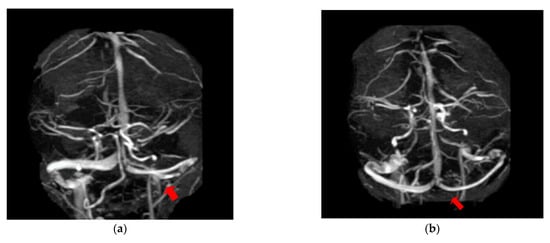

The first case, was a female, 26 years old, with an etiology of left otomastoiditis, hospitalized in superficial coma, with meningeal symptoms and HIC, psychomotor agitation and three generalized seizures. The Grisinger sign was present at local examination of mastoiditis. After a period of six months, at the reevaluation, the same patient did not present any residual symptomatology related to thrombophlebitis. The imagistic features can be seen in Figure 1 and Figure 2.

Figure 1. MR-venography 2D-TOF (2D- time of flight) in the coronal (a) and axial (b) plane noting the absence of the flow in the left lateral sinus (thrombosis of the left LS at the onset).